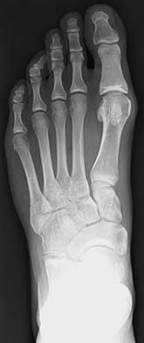

Figures 1a through 1c

Normal foot

Calcaneonavicular (CN) coalition

Talocalcaneal (TC) middle facet coalition

TC posterior facet coalition

- Calcaneonavicular (CN) coalition**_

Tarsal coalitions occur when primitive mesenchymal cells fail to differentiate and form the

normal articular separations between the tarsal bones of the hindfoot. Overall incidence is difficult to determine because many affected people are minimally symptomatic or asymptomatic. Symptomatic tarsal coalitions typically present in adolescents as a painful flatfoot; however, there are a number of possible presentations, and occasionally symptoms do not appear until adulthood. Most tarsal coalitions are between the calcaneus and the navicular (CN) and the talus and the calcaneus (TC). Although most TC coalitions are across the middle facet, posterior facet coalitions do occur. Plain radiographic evaluation of suspected tarsal coalition is the mainstay for diagnosis. However, coalitions can be bony or fibrous, and making the diagnosis can be difficult. The addition of CT images to distinguish bony definition and MR images to decipher soft tissue can aid in diagnostics. Bony coalitions appear as definite bony bridging between the bones, while fibrous coalitions are suspected when distortion of the bony anatomy is seen. Bony coalitions are best seen on the oblique view (CN) and Harris axial view (TC). There are a number of secondary signs such as the anteater (AE) sign (elongation of the anterior process of the calcaneus as it extends to the navicular as seen on the lateral view [CN]). talar beaking (traction spur of the talar neck thought to result from abnormal stresses as seen on the lateral view [both CN and TN]), and the “C” sign (a continuous cortical contour from the medial talus to the sustentaculum tali [ST]) as seen on the lateral view (TC). A number of newer signs are not as well known, such as a broad mediolateral dimension of the navicular on the anteroposterior (AP) view (the

navicular is wider than the talar head [CN]), nonvisualization of the middle facet on the lateral view (TC), the brick sign (a normal ST is flat, but a distorted ST is enlarged and curved [CN]), and a tapered lateral navicular bone as seen on the AP view (the medial navicular [CN] is much thicker than the lateral navicular).

Figure 1a shows talar beaking (TB), an AE, and an open middle facet (MF). Figure 1b shows a wide navicular (WN), and Figure 1c shows an abnormal articulation between the calcaneus and the navicular, all consistent with a CN coalition.